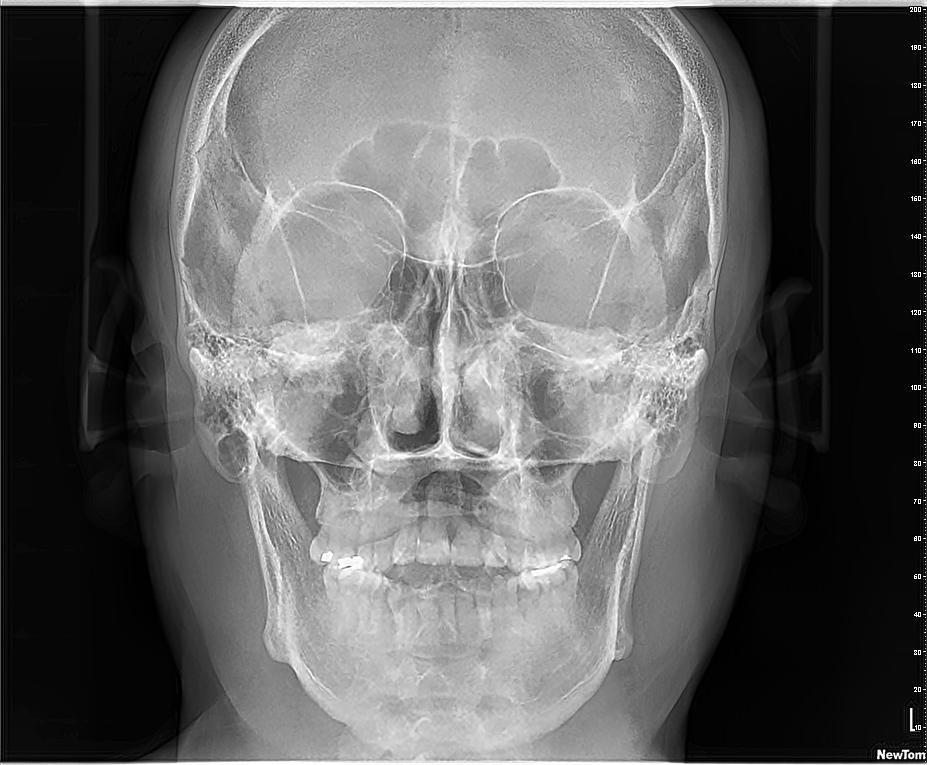

La radiografía de senos paranasales es una técnica de imagen que se utiliza para examinar las cavidades llenas de aire en los huesos que rodean la nariz, conocidas como senos paranasales. Incluyen los senos maxilares, etmoidales, esfenoidales y frontales. Puede ser realizada para diversos propósitos, como:

- Evaluación de la anatomía

- Detección de tumores o quistes

- Evaluación de fracturas